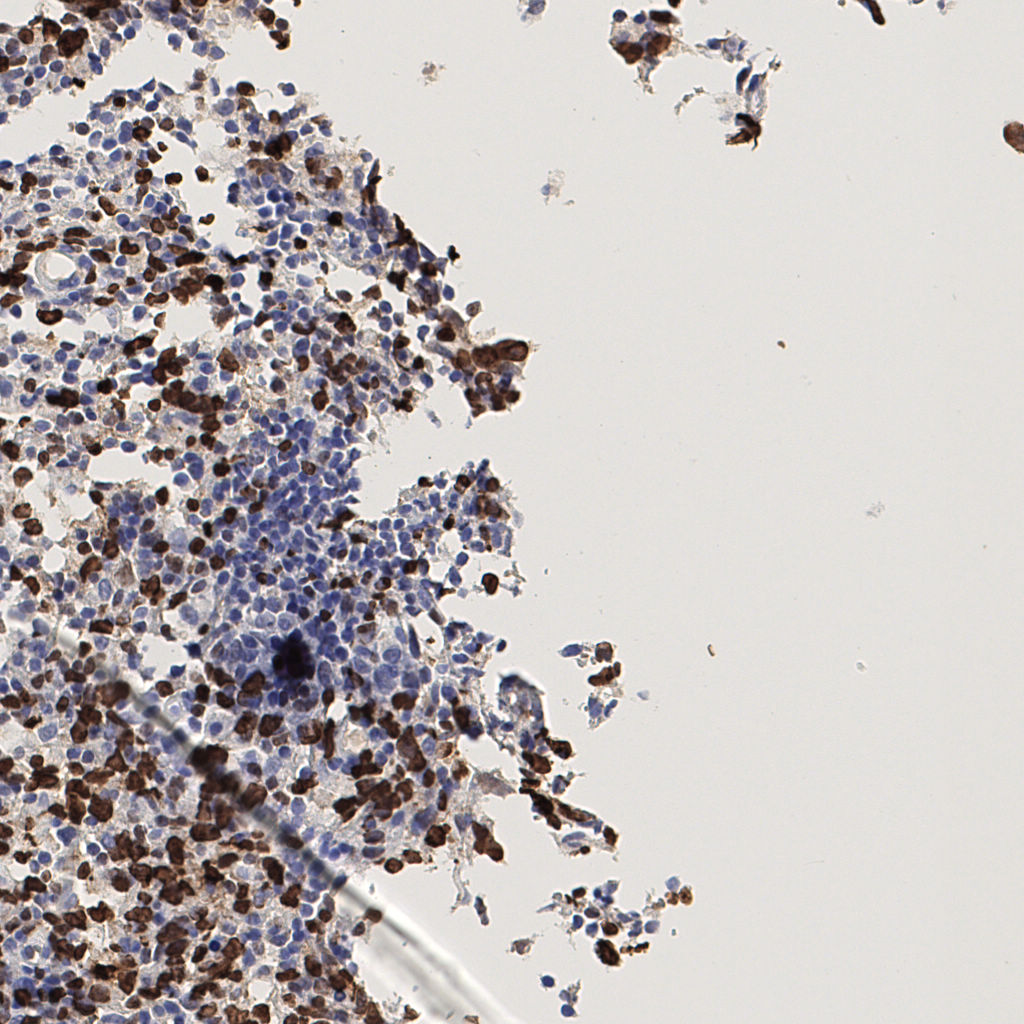

7.85%

Ki67 指数

阴 1104 阳 94

切片统计

总切片 1953

有效 288

已标记 288

有效率 15%

H255858-KI-67.ndpi